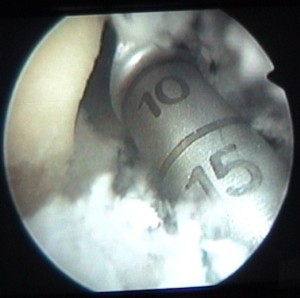

on voit la tête de la vis au milieu de la clé plate |

et le corps de la vis en-dessous |

cette vis sert à attacher le ligament |

et elle est maintenant vissée à fond |